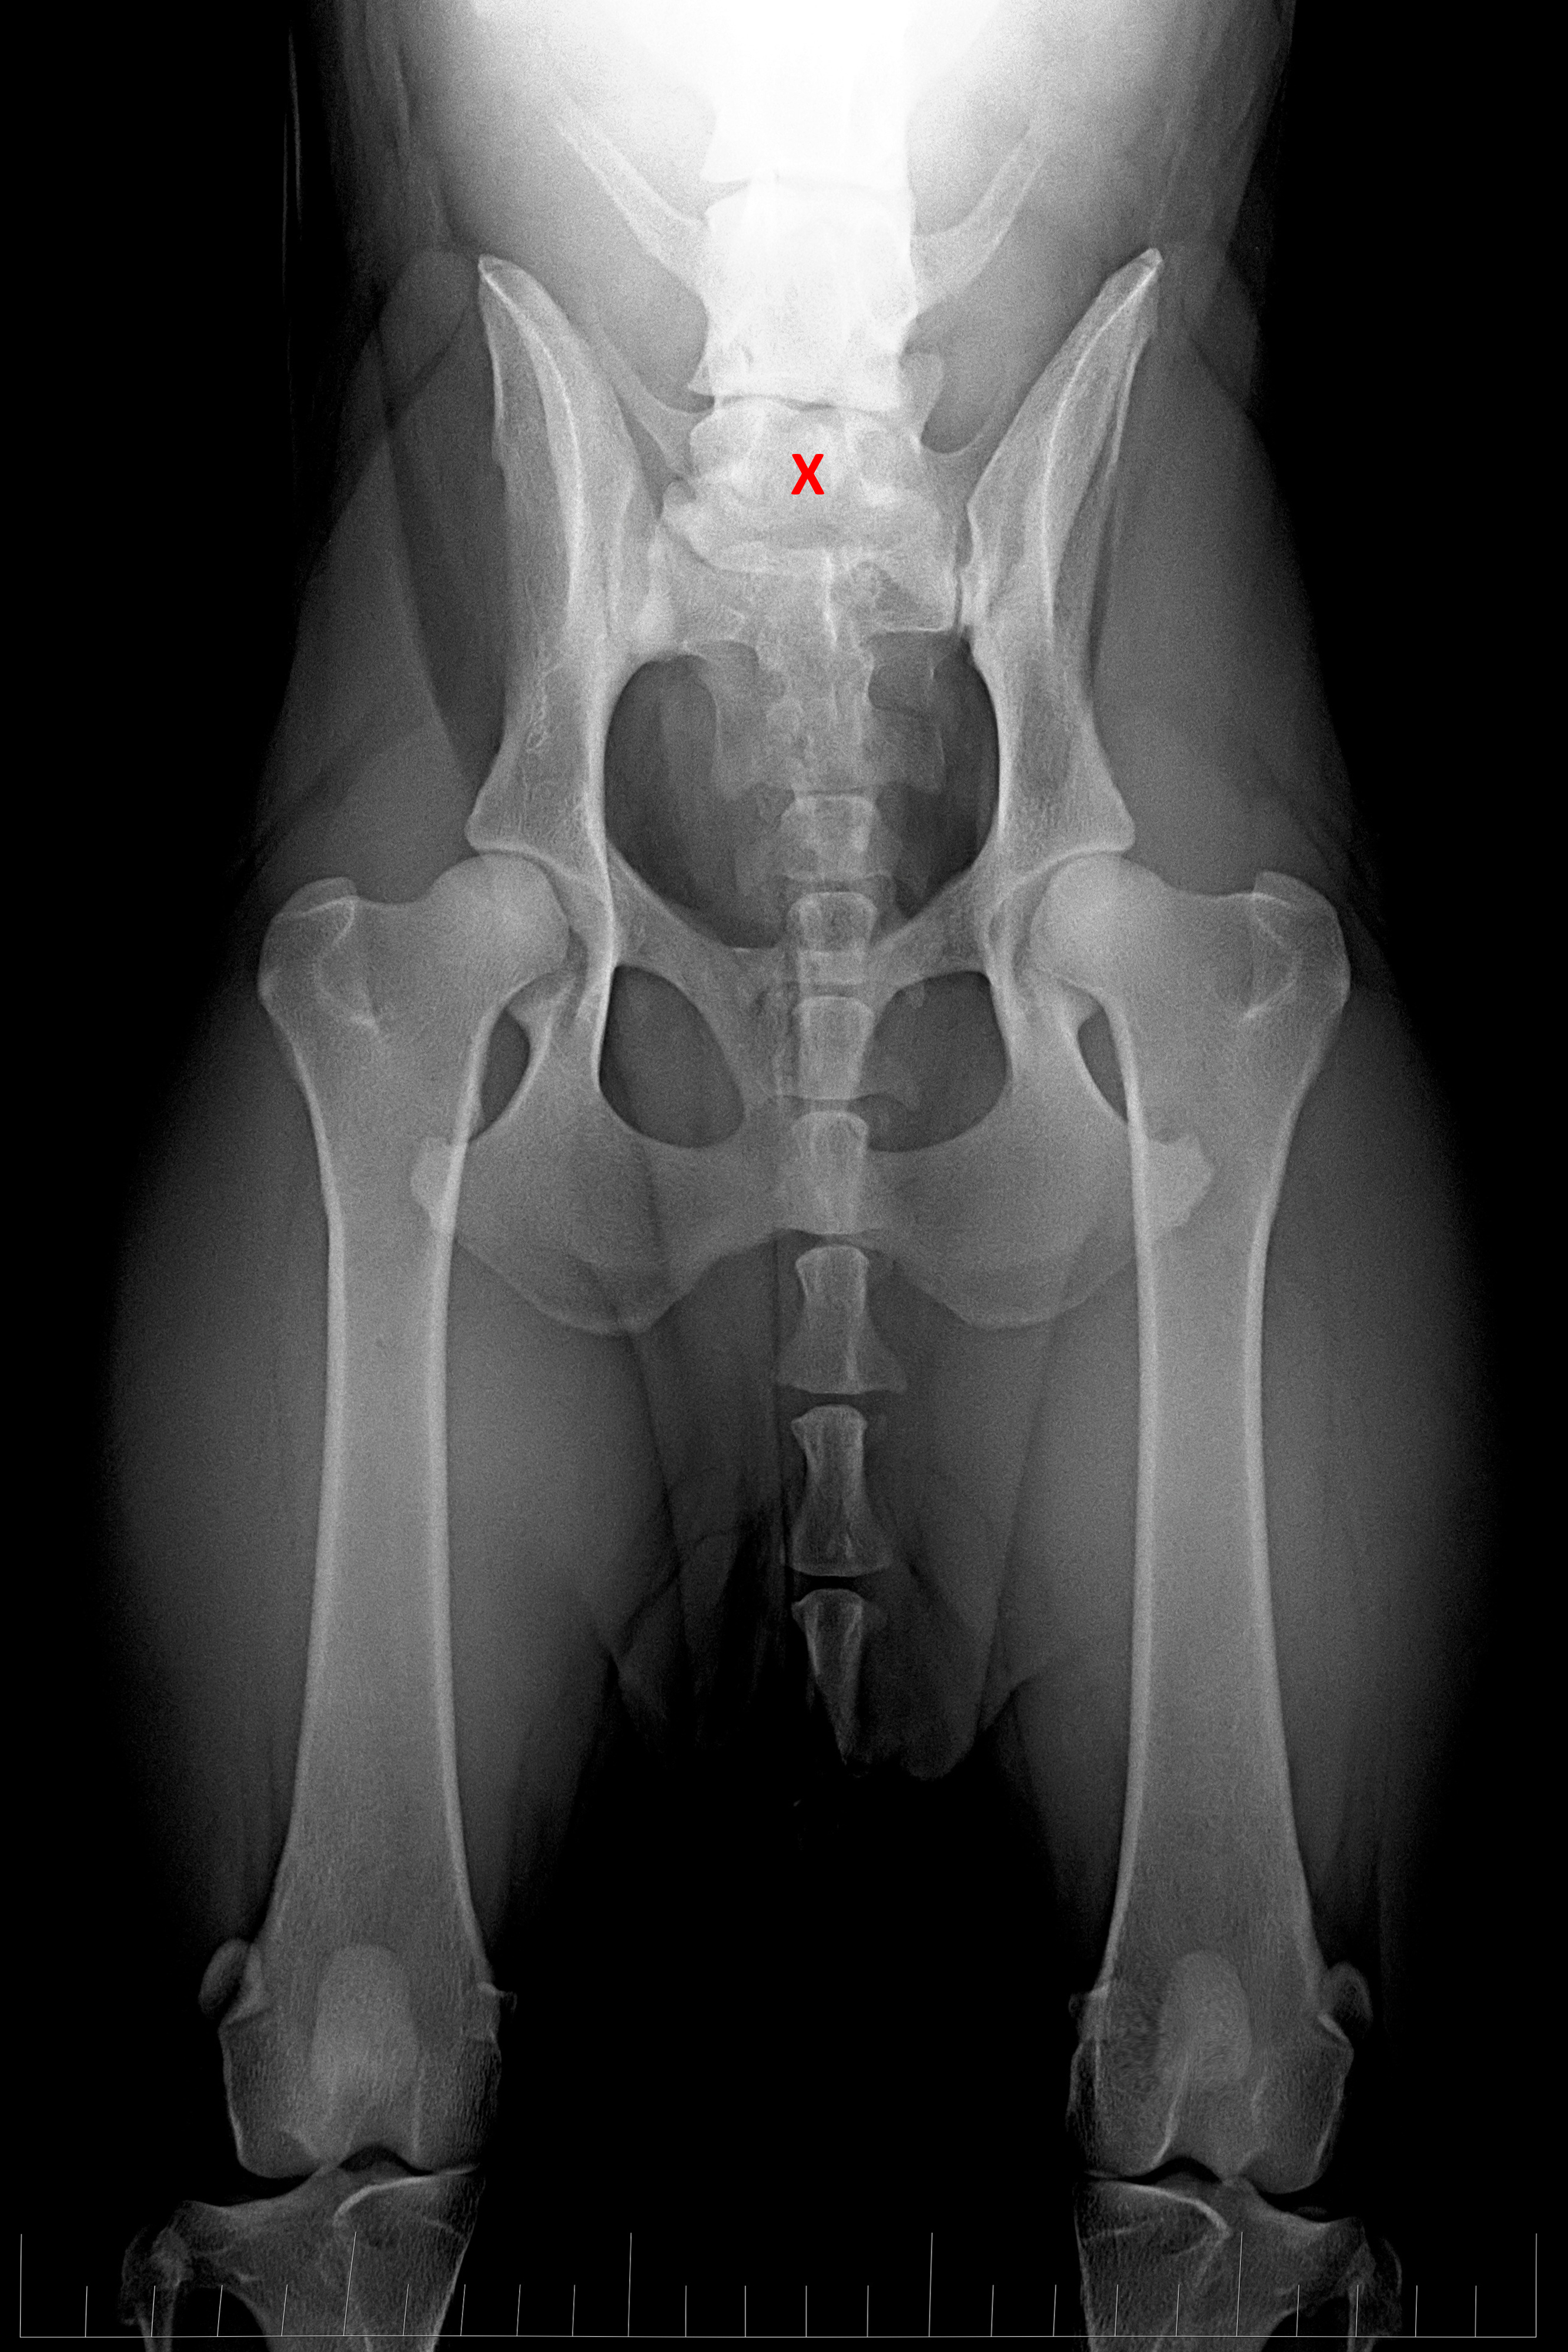

(3) 7 měsíců VD 1

(3) typ 3 po korekci polohy pánve

(4) 7 měsíců VD 2

(4) typ 3 po korekci polohy pánve 2